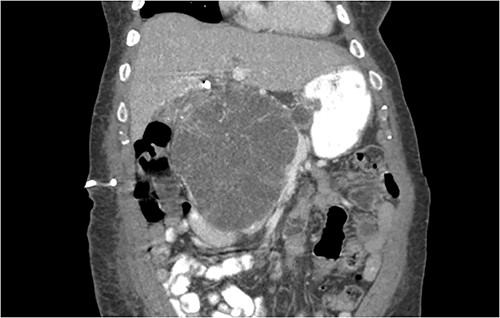

Another abdominal CT was performed redemonstrating the large heterogenous mixed attenuating mass within the right abdomen measuring 14.0 × 10.0 × 13.0 cm likely originating from the pancreatic head with resultant displacement of the PTC anteriorly and to the right with extensive pancreatic ductal dilation (Figs 2 and 3).

Coronal CT showing a large heterogeneous mass in the pancreatic head with typical honeycomb feature.